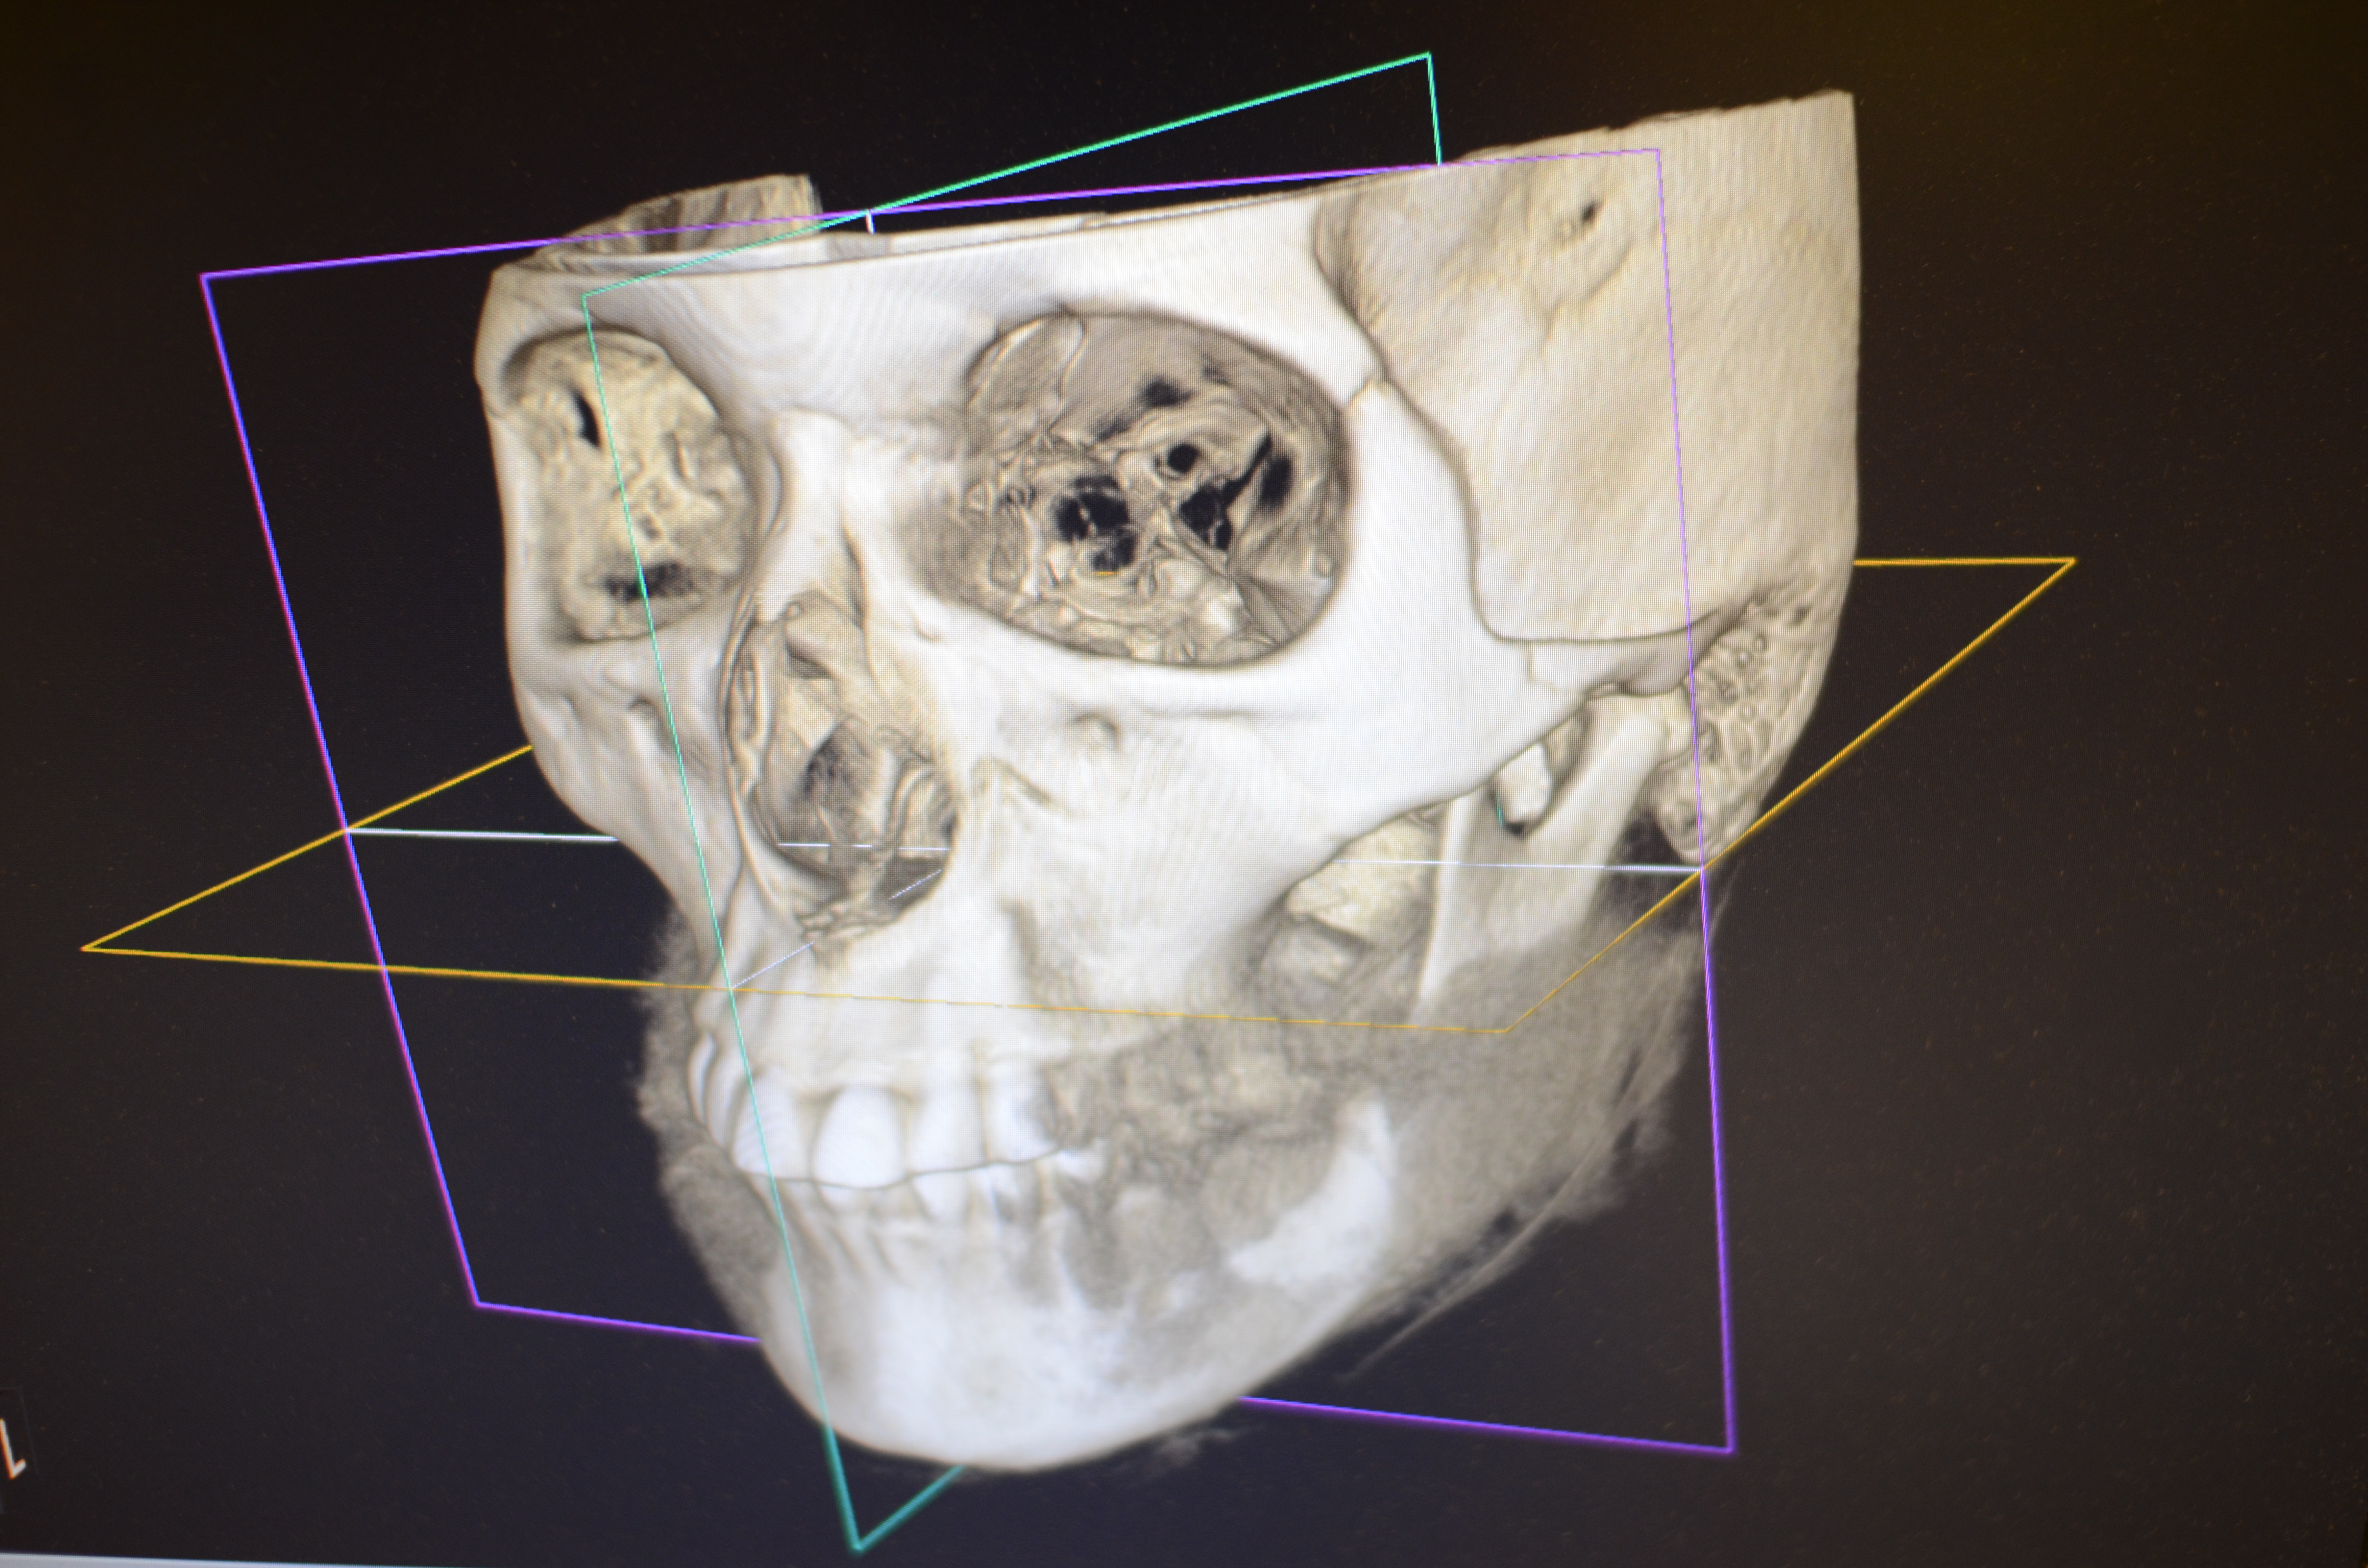

サージカルガイドを用いたインプラント治療

事前にCT撮影と歯型をとり、理想的な位置にインプラントを埋入できるように、サージカルガイドというマウスピースのようなものを作成してから手術を行います。

このレントゲン写真のように理想的な位置にインプラントが設置できます。

CT画像による診断

CTデータを実際の口腔内模型と合成し、インプラント埋入のシミュレーションを行います。